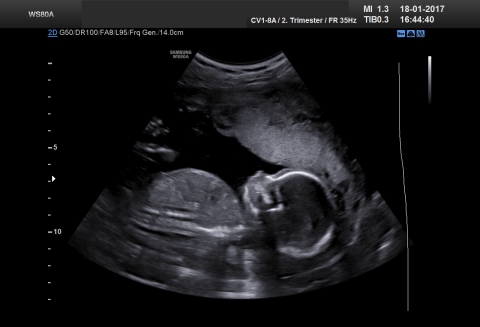

Grösse (Scheitel-Steiss-Länge): 140 mm

Gewicht: ca. 200-220 g

Kopfdurchmesser: 38-48 mm